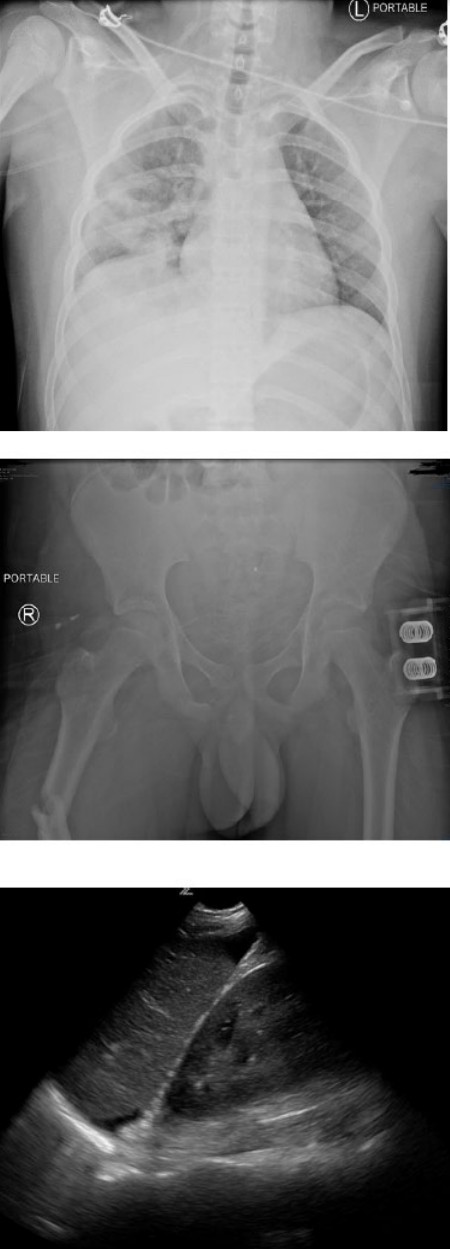

During primary survey, GCS deteriorates to 7 (E1, V2, M4) and decision is made to intubate. A skeletal survey and eFAST are performed with images shown in the PDF.

A skeletal survey and eFAST are performed.

3. List (4) significant diagnoses for this patient and your clinical reasoning for your diagnoses. 8 marks